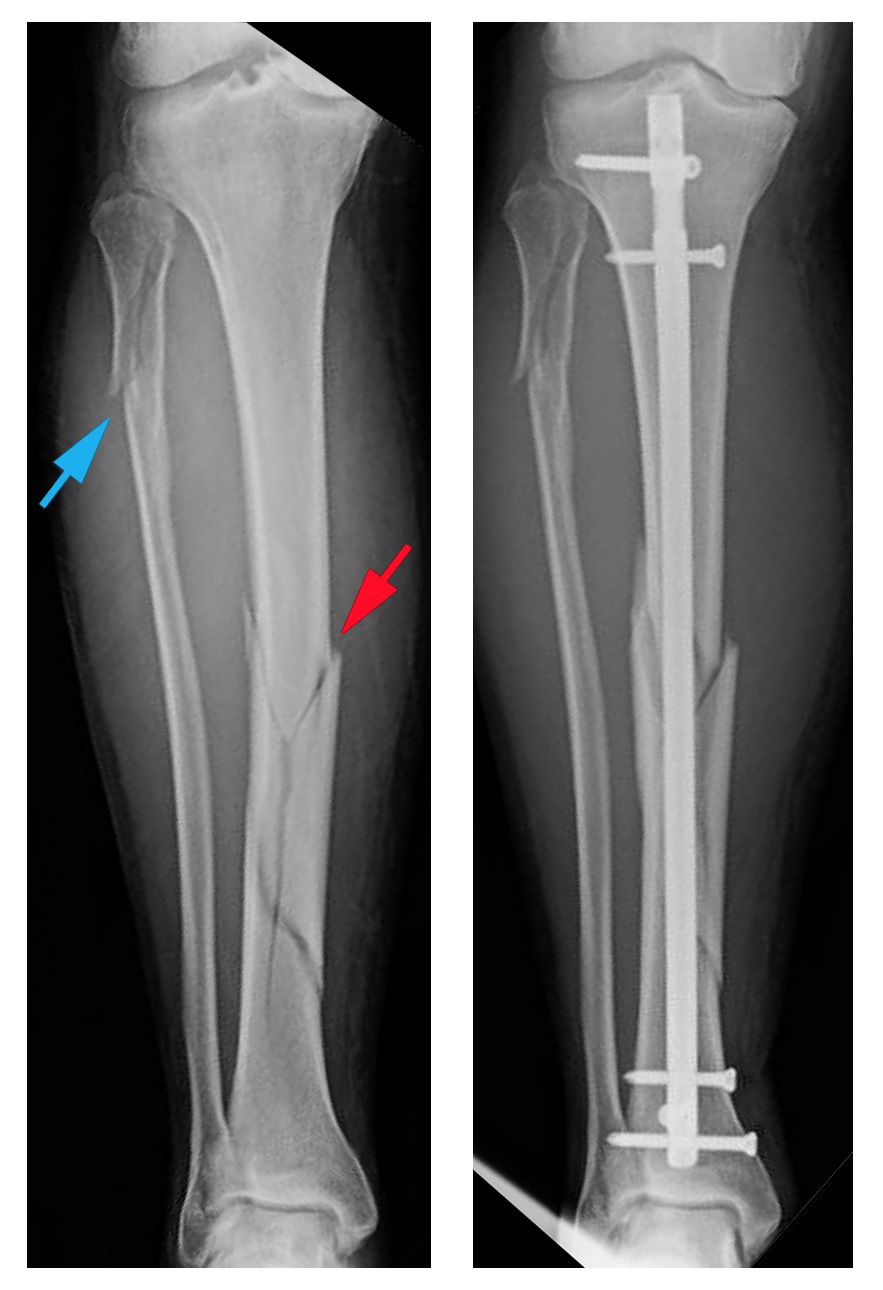

Intramedullary nailing. Currently, the method most surgeons use for treating tibia fractures is intramedullary nailing. During this procedure, a specially designed metal rod (nail) is inserted inside the tibia. The nail passes across the fracture to keep it in position.

Screws are used to stabilize the nail at both ends (top and bottom). This keeps the nail and the bone in proper position during healing.

Intramedullary nailing of a tibial shaft fracture

Intramedullary nailing provides strong, stable, full-length fixation.

Intramedullary nails are usually made of titanium. They come in various lengths and diameters to fit most tibia bones.

X-rays of tibial shaft fracture and intramedullary nailing

(Left) X-ray shows a tibial shaft fracture (red arrow) and a fibula fracture (blue arrow). (Right) The tibial shaft fracture has been treated with intramedullary nailing.

Intramedullary nailing is not ideal for fractures in children and adolescents because care must be taken to avoid crossing the bone's growth plates.